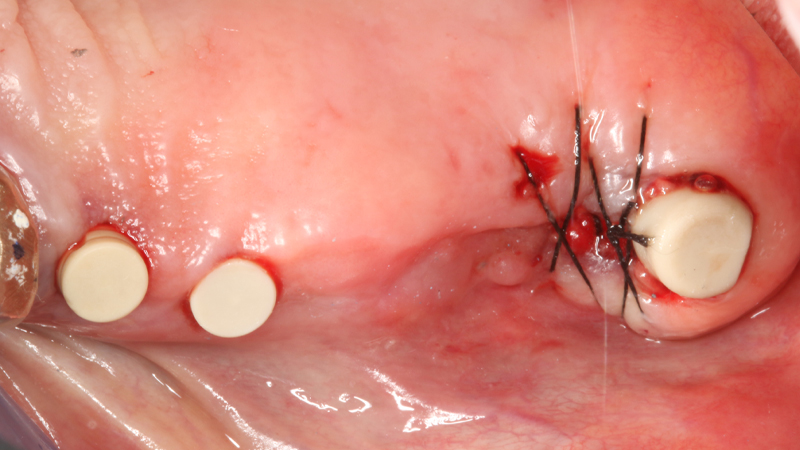

Sul 12 veniva eseguito un impianto post-estrattivo con carico immediato mediante moncone conometrico e provvisorio ricavato ribasando una cappetta provvisoria in peek e applicazione a frizione mediante conometria (Figs. 19, 20, 21, 22, 23).

Carico immediato su 12 con moncone conometrico dritto e cappetta provvisoria in peek ribasata in resina su provvisorio. Foto dopo l'intervento con esecuzione flapless e leggera plastica gengivale del Tuber applicazione di cappette di guarigione in peek. Guarigione dei tessuti dopo 3 mesi e impronta digitale definitiva per finalizzare il caso

Fig. 19, 20 - Carico immediato su 12 con moncone conometrico dritto e cappetta provvisoria in peek ribasata in resina su provvisorio. Foto dopo l'intervento con esecuzione flapless e leggera plastica gengivale del Tuber applicazione di cappette di guarigione in peek. Guarigione dei tessuti dopo 3 mesi e impronta digitale definitiva per finalizzare il caso

Fig. 21 - Carico immediato su 12 con moncone conometrico dritto e cappetta provvisoria in peek ribasata in resina su provvisorio. Foto dopo l'intervento con esecuzione flapless e leggera plastica gengivale del Tuber applicazione di cappette di guarigione in peek. Guarigione dei tessuti dopo 3 mesi e impronta digitale definitiva per finalizzare il caso

Fig. 22 - Carico immediato su 12 con moncone conometrico dritto e cappetta provvisoria in peek ribasata in resina su provvisorio. Foto dopo l'intervento con esecuzione flapless e leggera plastica gengivale del Tuber applicazione di cappette di guarigione in peek. Guarigione dei tessuti dopo 3 mesi e impronta digitale definitiva per finalizzare il caso

Fig. 23 - Carico immediato su 12 con moncone conometrico dritto e cappetta provvisoria in peek ribasata in resina su provvisorio. Foto dopo l'intervento con esecuzione flapless e leggera plastica gengivale del Tuber applicazione di cappette di guarigione in peek. Guarigione dei tessuti dopo 3 mesi e impronta digitale definitiva per finalizzare il caso